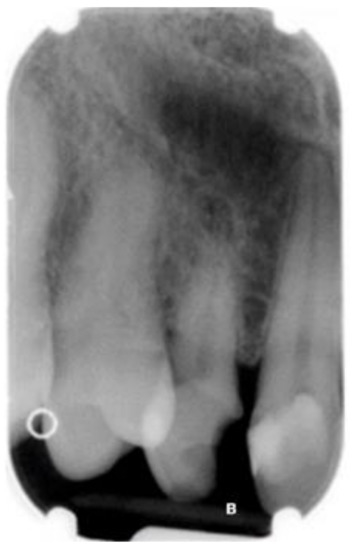

| (a) Surgical removal of the deciduous tooth and orthodontic extrusion, and taking in occlusion of the permanent canine |

| (b) Conservative treatment of the deciduous tooth living in situ with the impacted canine |

| (c) Removal of the deciduous tooth and involvement of the adjacent natural elements for a fixed conventional or adhesive bridge living in situ with the impacted canine |

| (d) Removal of the deciduous tooth and replacement with implant-borne-prosthesis living in situ with the impacted canine, accepting the compromise of involving the impacted tooth in the implant seating procedure |

| (e) Surgical removal of the impacted canine and, in a second stage, removal of the deciduous tooth and replacement with implant-borne-prosthesis |